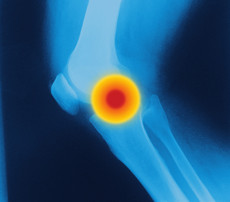

Oldenburg - Die präventive und therapeutische Effizienz von Pycnogenol®, dem Extrakt aus der französischen Meereskieferrinde, auf die Gelenkgesundheit ist unbestritten. Die bioaktiven Metaboliten von Pycnogenol®, wie die antioxidativ wirksamen Polyphenole, sind nach einer dreiwöchigen Einnahme von täglich 200 mg Pycnogenol® in der Synovialflüssigkeit im Kniegelenk von Osteoarthritis-Patienten nachzuweisen.

Die präventiven und therapeutischen Wirkungen des pflanzlichen Extraktes Pycnogenol® auf Symptomverbesserungen sowie Reduktion des Analgetikagebrauchs bei Osteoarthritis wurden in klinischen Studien bestätigt. Die Patienten berichten von einem neuen Lebensgefühl, die Lebensqualität konnte deutlich gesteigert werden.

Die antiinflammatorische Wirkung von Pycnogenol® erreicht über die Hemmung des Entzündungsmarkers CRP von mehr als 70 Prozent eine deutliche Verringerung der freien Radikale um bis zu 30 Prozent. Als starkes Antioxidans stimuliert der polyphenolreiche Extrakt die Synthese antioxidativ wirksamer Enzyme wie Katalase, Superoxiddismutase und Glutathion. Gleichzeitig bindet Pycnogenol® freie Radikale und zerstört deren Oxidationspotenzial. Die in dem Extrakt enthaltenen Wirkkomponenten sind in hohem Maße bioverfügbar. Durch die Synergie der enthaltenen Wirkstoffe verstärkt sich die präventive und therapeutische Effizienz im Vergleich zu den Einzelwirkstoffen.